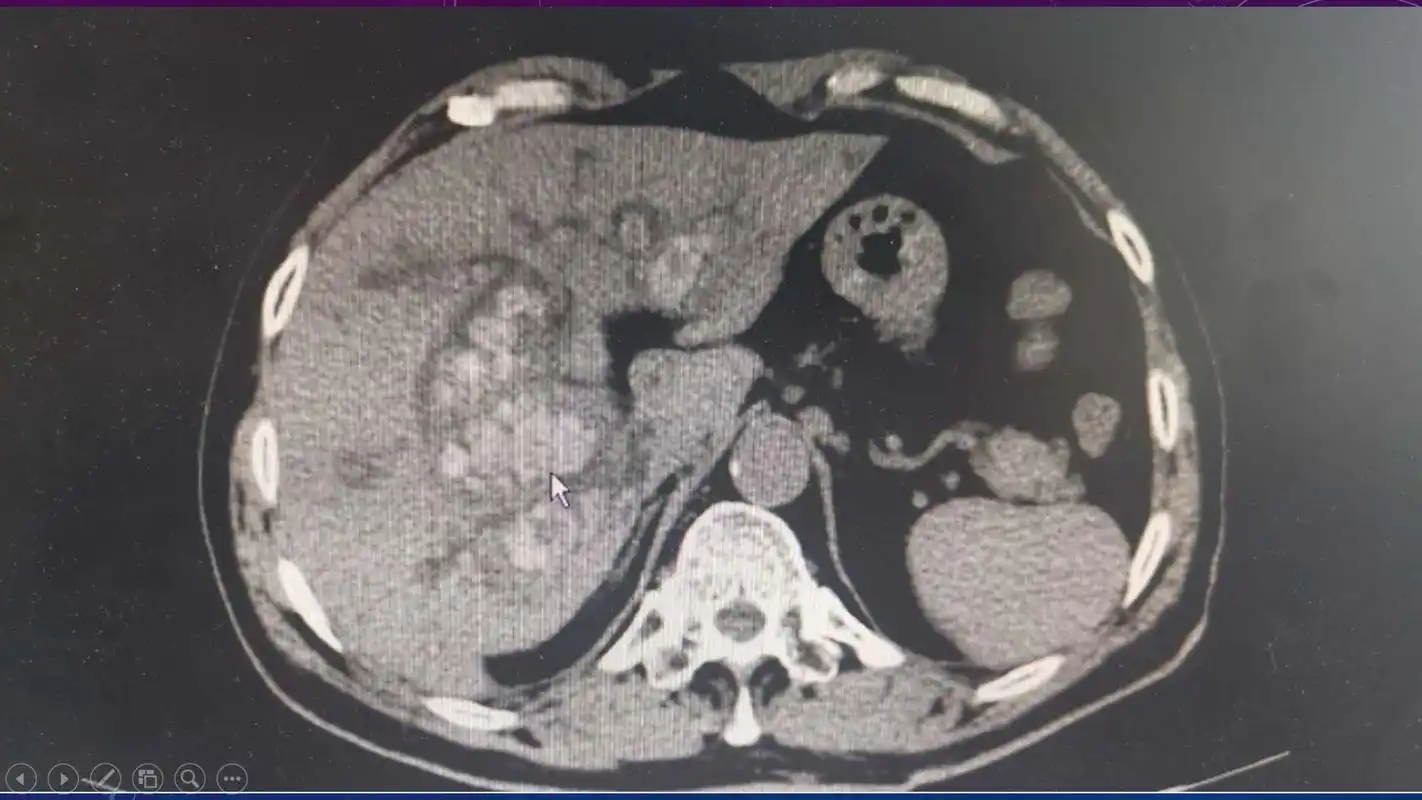

一例充满型胆囊结石的保胆治疗

ct值在50hu以上,单发或多发,形态,大小各异,泥沙样结石常沉积在胆囊

部分胆囊结石ct可显影

上腹ct见胆囊结石,胆囊明显胀大.

类圆形或多角形;ct值在40hu以下,变换体位结石位置有变动,少数与胆囊